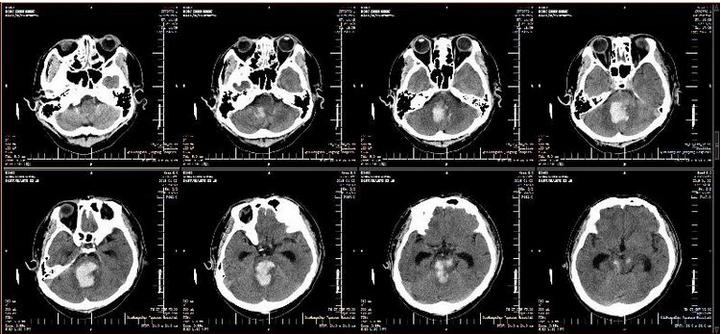

2019年1月2日,军工医院副院长于笑鹏协调急诊科、重症医学科、神经外科、手术室麻醉科做好转接手术患者相关准备工作,紧急召集120急救人员与该医院沟通,将患者接到重症医学科进行术前准备。患者来院后复查头CT显示:脑干内血肿量较前明显增多,出现梗阻性脑积水征象。在院领导的关注下,神经外科医生团队经过两个多小时的精湛手术,患者生命体征平稳。复查头CT显示:脑干内血肿清除彻底,脑积水解除,转回军工医院重症医学科继续治疗。术后6小时,患者自主呼吸恢复,有吞咽动作,格拉斯评分由入院前3分转为5分,各种刺激检测均有反应。

术后头CT片